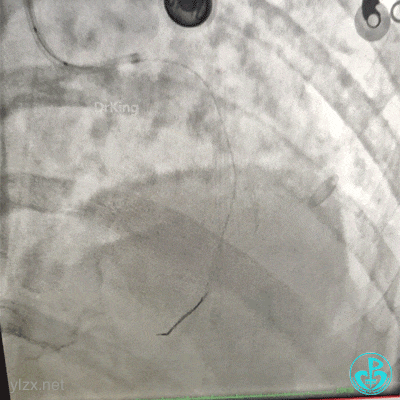

2.0×15mm球囊预扩张后。

植入4.0×13mm支架1枚。